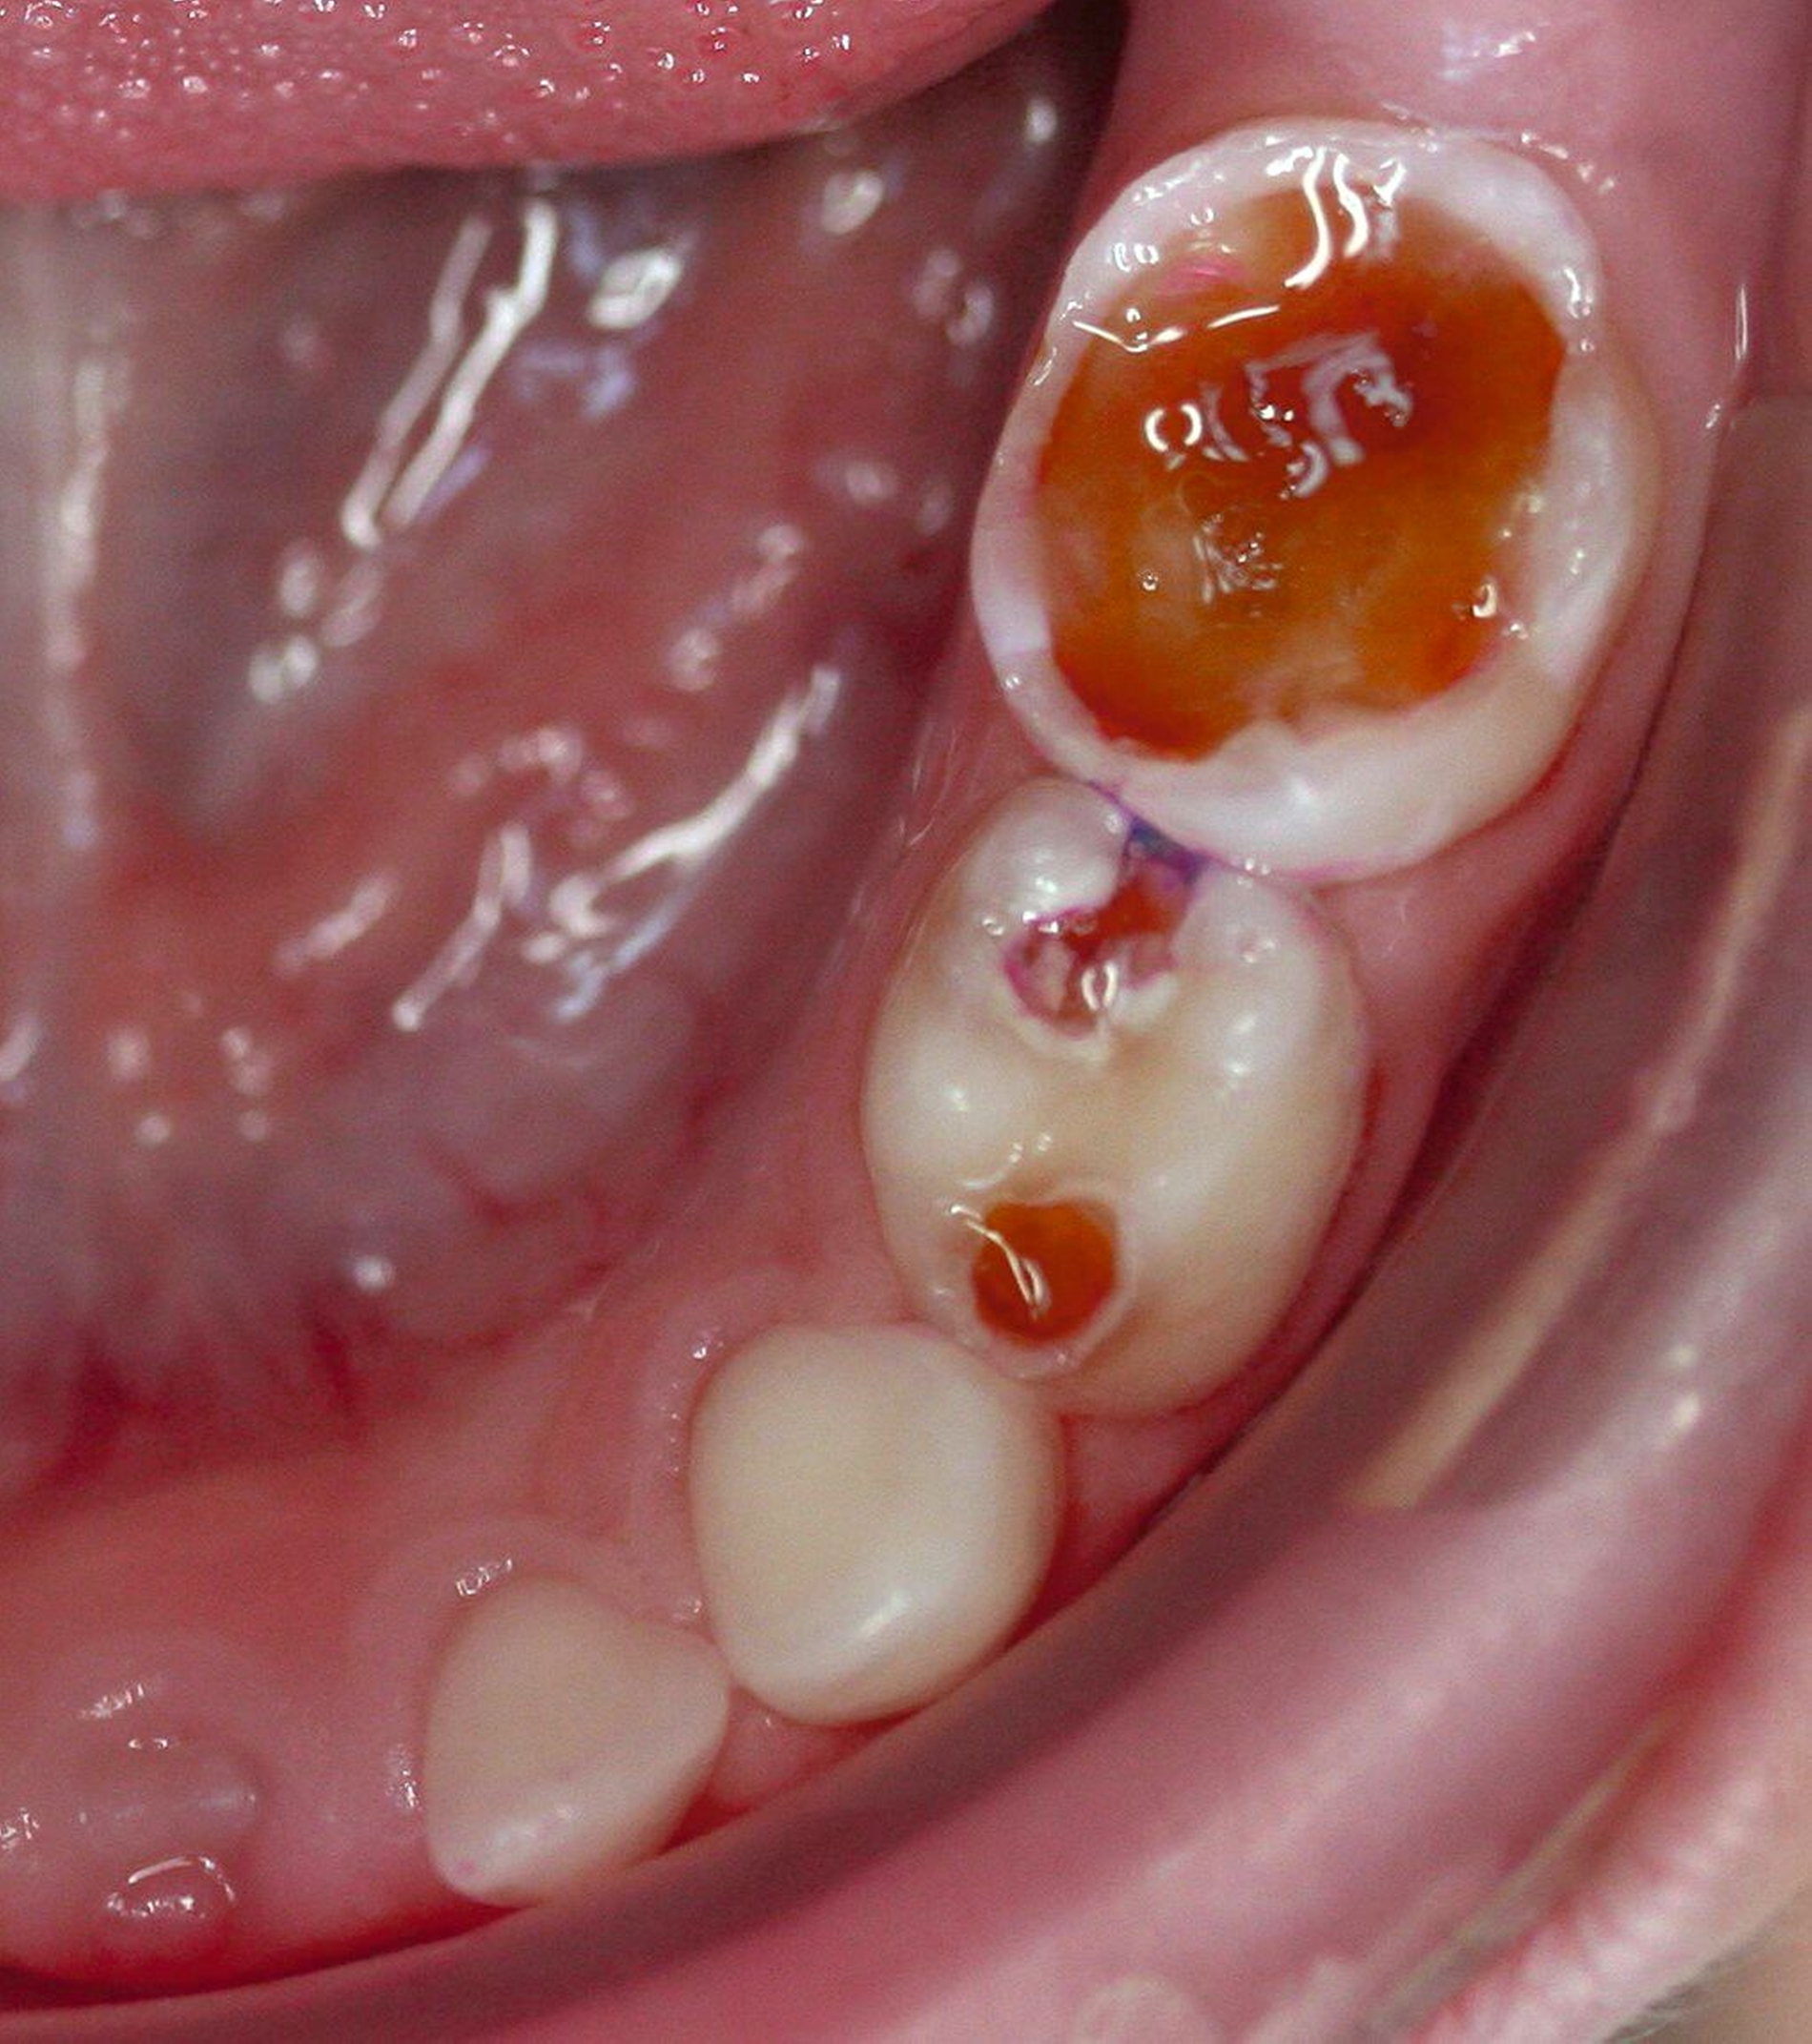

SDF ist besonders wirksam bei der Behandlung von Kariesläsionen (Abbildung 1). Bei der Anwendung auf kariösem Zahnhartgewebe dringen die Silberionen in die bakteriellen Zellwände ein, stören die bakterielle DNA-Synthese und den Stoffwechsel, und führen so zum Zelltod. Zusätzlich stabilisieren die Silberionen die kariösen Läsionen, indem sie die Dentinkanälchen blockieren (Abbildung 2) [Crystal, and Niederman, 2019].

Es ist zu beachten, dass SDF die (Mundschleim-)Haut und die Gingiva vorübergehend verfärben kann, weshalb der Kontakt mit diesen Geweben während der Anwendung vermieden werden sollte (Abbildung 3). Eine Isolierung, zum Beispiel mit flüssigem Kofferdam, ist eine Option (Abbildung 4). Da die Mitarbeit der Kinder oft gering ist, sollten zumindest die Lippen vorher mit Vaseline eingecremt werden, um unbeabsichtigte extraorale Verfärbungen zu reduzieren.

Bei der Behandlung von Patienten mit besonderen Bedürfnissen scheint sich der Schwerpunkt der präventiven und restaurativen Strategien zu verlagern, indem minimalinvasive Methoden wie SDF und die Hall-Technik eingesetzt werden (Abbildung 5). Minimalinvasive Therapien haben sich als geeignet und wirksam für die Behandlung von Kariesläsionen sowohl bei Milchzähnen als auch an bleibenden Zähnen erwiesen und reduzieren somit die Notwendigkeit von Eingriffen unter Vollnarkose [Molina et al., 2022].